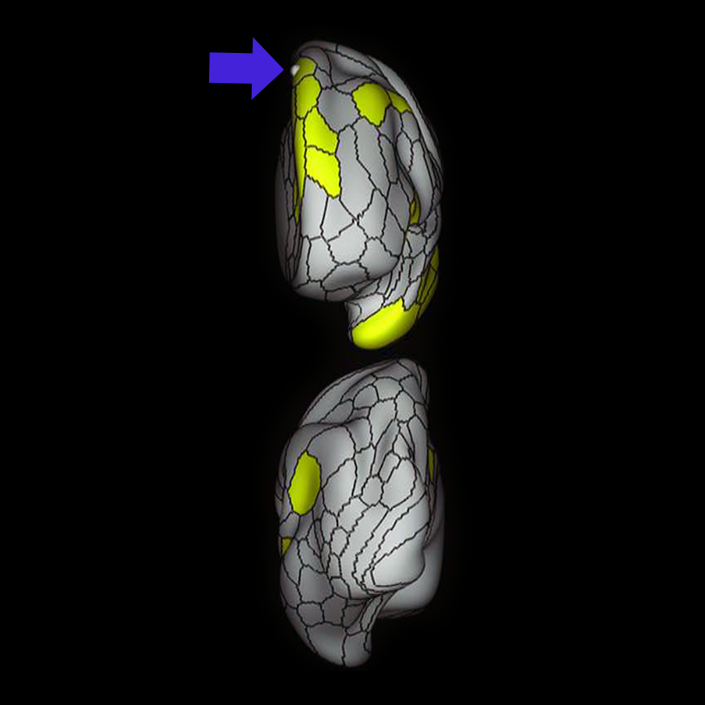

ᐅ SummaryArea 44: part of the inferior frontal gyrus of the lateral frontal lobe. Translates abstract and intentional information in the prefrontal cortex to more detailed representations to help guide the production of verbal and manual actions. In addition to its known association with Broca's area, is sometimes represented as part of Broca's complex ᐅ Where is it?Area 44 is at the posterior most part of the inferior frontal gyrus. It is the anterior bank of pars opercularis of the IFG. ᐅ What are its borders?Area 44 borders area 45 anteriorly and area 6r posteriorly. Area 8C is its medial border and its inferior border is wedged between then upper borders of Areas 6R and 6V. Its superior edge borders IFSp and IFJa. Its opercular surface is FOP4. ᐅ What are its functional connections?Area 44 demonstrates functional connectivity to areas SFL, IFSp, IFJa, 45, 47s, 47L, 9a, 9m, 8AV, 8BL and 8C in the dorsolateral frontal lobe, area 8BM in the medial frontal lobe, area 55b in the premotor areas, areas FOP5, AVI and PSL in the insula- opercular region, areas TGd, STSdp and STSvp in the temporal lobe, areas PFm, and PGi in the inferior parietal lobe, and no areas in the medial parietal lobe. ᐅ What are its white matter connections?Area 44 is structurally connected to the arcuate/SLF and the FAT. Connections with the arcuate/SLF project posteriorly and wrap around the Sylvian fissure to the middle temporal gyrus to end at TE1a and TE1m. There are also projections from the arcuate/SLF before it terminates to parcellations A5 and STSdp. The majority of the inferior connections of the frontal aslant tract end at 44, the tract is connected superiorly to superior frontal gyrus parcellations SFL, 6ma and s6-8. Local short association bundles are connected with 45 and 8C. White matter tracts from 44 in the right hemisphere have less consistent connections with the arcuate/SLF. ᐅ What is known about its function?Area 44 translates abstract and intentional information in the prefrontal cortex to more detailed representations to help guide the production of verbal and manual actions. Area 44, in addition to its known association with Broca's area, is sometimes represented as part of "Broca's complex", including Brodmann Areas 45, 46, 47 and the mesial supplementary motor area of 6, which contribute to a frontal-subcortical circuit. The right pars opercularis has also been implicated in cognitive inhibition in the overall context of working memory. |

A: lateral-medial

B: anterior-posterior

C: superior-inferior

DTI image |